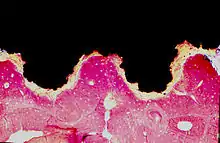

An osseointegrated implant is a type of implant defined as "an endosteal implant containing pores into which osteoblasts and supporting connective tissue can migrate".[2] Applied to oral implantology, this refers to bone grown right up to the implant surface without interposed soft tissue layer. No scar tissue, cartilage or ligament fibers are present between the bone and implant surface. The direct contact of bone and implant surface can be verified microscopically.